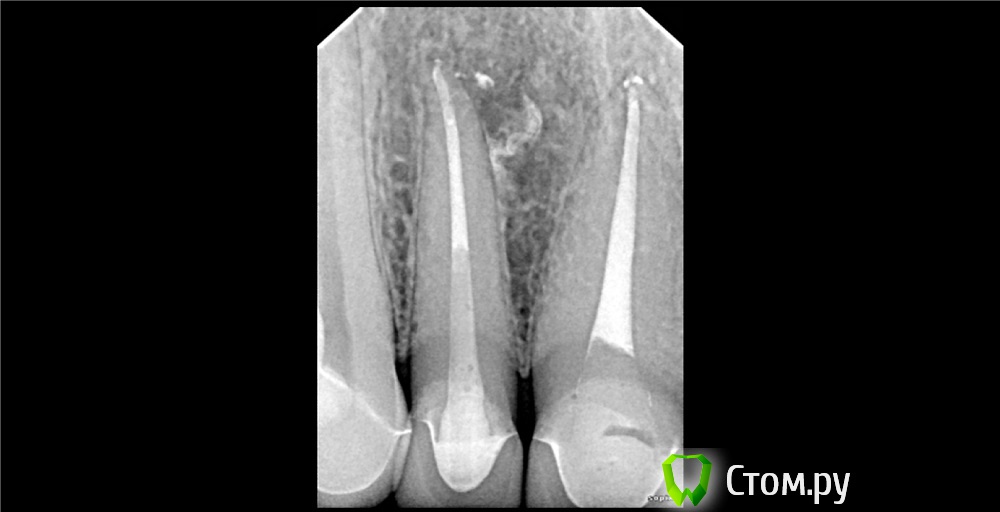

Dr.Sham Опубликовано 9 ноября, 2014 Поделиться Опубликовано 9 ноября, 2014 (изменено) Пришла пациентка за винирами, сделали снимки, увидили красоту Виниры на время отложили.Начал лечить, получил обострение, отмылся повторно, симптомы ушли.2 раза кальций поменял, т.к. после первого раза еще канал влажный был.Запаковал или волной, или сквирт был, уже не вспомнить.Вот результаты, критикуйте 05.1209.1311.14 Изменено 9 ноября, 2014 пользователем Dr.Sham 11 Ссылка на комментарий

M@estro Опубликовано 9 ноября, 2014 Поделиться Опубликовано 9 ноября, 2014 Перепреп детектед а так норм Ссылка на комментарий

Shaid Опубликовано 10 ноября, 2014 Поделиться Опубликовано 10 ноября, 2014 Перепреп детектед Имеется ввиду овер в 1.2 или чрезмерное расширение устьевой и средней части в 1.1? Ссылка на комментарий